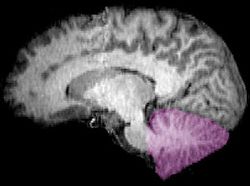

الشكل 1b: صورة تصوير الرنين المغناطيسي تبين منظراً mid-sagittal للمخ البشري، ويبدو فيه المخيخ باللون البنفسجي من , , , http://www.marefa.org/index.php/صورة:Neuro_logo.png